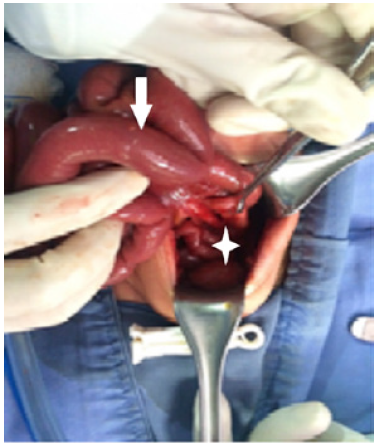

Invasive ventilation was initiated and a nasogastric tube was passed in-situ. An abdominal x-ray showed a large dilated loop of bowel (Figure 2), without a double bubble sign, ruling out duodenal atresia. Based on those findings, in her third day of life, an exploratory laparotomy was performed. A right colon atresia type III (Grosfeld classification) 11 was identified, with a difference of proximal distal caliber from 10 to 1 (Figure 3). A derivative Hartmann's colostomy was performed, given the difference of caliber size that did not allow primary anastomosis. Rectal biopsies were taken, reporting ganglion cells and ruling out Hirschsprung's disease.

During surgery, a discrepancy of calibers from 5 to 1 was observed and lateral anastomosis with a mechanical lineal suture was performed, leaving a colonic lateral window diversion proximal to the anastomosis, which is useful in cases of extreme size discrepancy. 12 During the third surgery, the protective colostomy was closed, observing hermetic anastomosis, with no stenosis. Post-surgical evolution was good, and the patient was discharged three days after surgery. No other abnormalities associated with this patient were observed. After 2 years of follow-up, no complications and daily normal evacuations were reported.